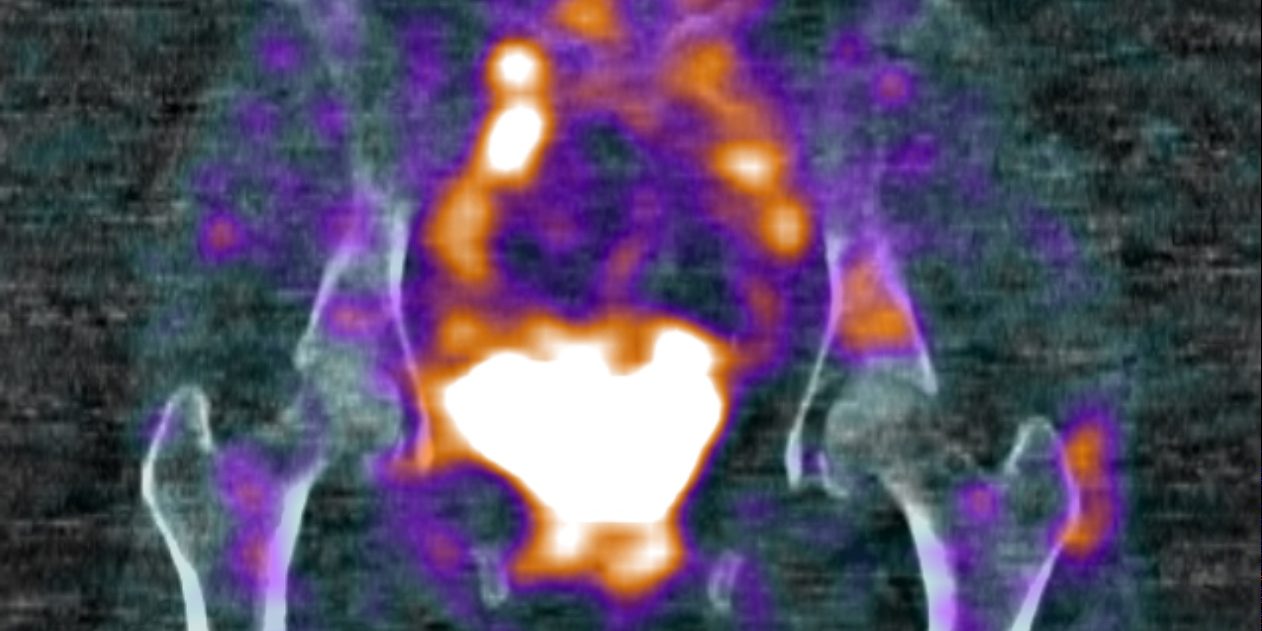

There are several challenges facing us when performing a bloodpool phase SPECT-CT. For instance, the patient may need to be repositioned between the dynamic acquisition and the blood pool phase SPECT-CT. There are also limitations on the camera usage, which can be a problem if you have only one SPECT-CT scanner available in your department. These scans are also trickier to report. Normal bloodpool phase activity needs to be re-learnt, including the normal vascular anatomy. The thresholding of the scans can be difficult when displaying the bloodpool phase due to the intense vascular activity and urinary bladder activity. Often the bloodpool activity in the soft tissues and bone can be low grade and much less intense than the urinary activity. The bloodpool phase SPECT-CT allows us to evaluate the soft tissues as well as the bones when performing a bone scan. Therefore, it is important to know the anatomy well and have a thorough understanding of the musculoskeletal pathology. For instance, we can identify tendinopathy and ligamentous injuries with bloodpool phase SPECT-CT that we would not have previously with planar imaging.